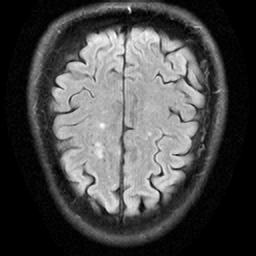

Fig. 2: Results on Denoising (Top row) and Super-Resolution (Bottom row) tasks using DiffPIR. We demonstrate perceptually comparable performance of our diverse prior in both patch-based (DiffPIRfull{}_{\text{full}}) and patch-based DiffPIRpatch{}_{\text{patch}} training.

4.1 Patch-wise trained models offer comparable performance to whole image models

As seen in Table 1, we demonstrate that our patch-wise trained prior offers comparable performance to a model trained at full image size. Specifically, when our model trained with patch size 128×128128\times 128 are used in whole image mode for plug-and-play, their performance is comparable to our whole image trained model, although the later is still slightly better. This is illustrated further in Fig. 2. This highlights that patch-based training could be an effective alternative when medical image resolutions grow (for example, ultra high resolution CTs) to render whole image training memory-intensive or even infeasible.